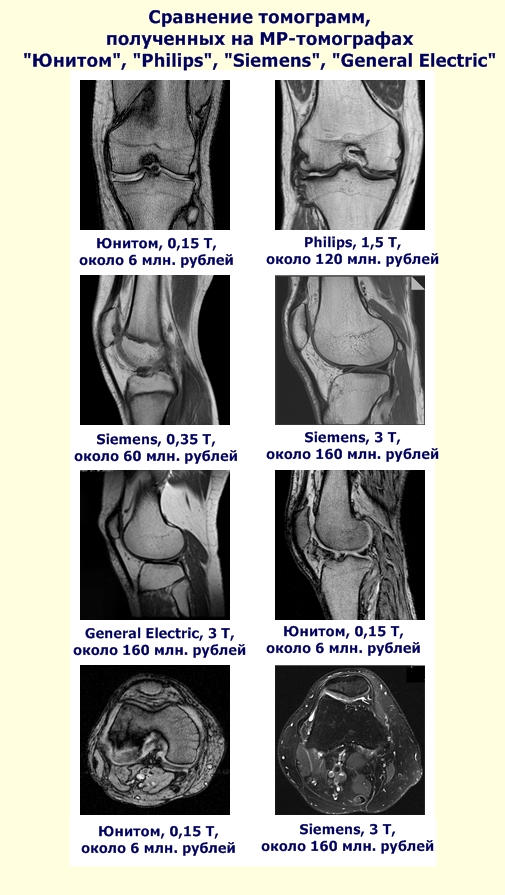

The world's first fully digital magnetic scanner . Suffice it to say that in a second measurement is recorded and processed one billion bits of data in real time. The use of the latest technological advances brought results: obtained image quality is not worse than on costly foreign imagers . Prices of the last times and reach 160 million rubles. The problem of high prices has become known throughout the country thanks to the president's robust language.

Public MRI scanner - scanner "Unitom" - no need for expensive cryogenic materials for his service . He is the most "green" scanner: its power consumption compared to foreign energy high field scanners below 100 (!!!) times. So, scanner can be powered by solar panels, even ! The size of the room where you can set the "Unitom", a fraction of the size of the room required for the traditional foreign MRI. Also, thanks to the many innovative solutions, Public MRI scanner is only 6 million rubles .

Take our scanner. Many also did not believe in creating it. There is no government funding we have received. But today the scanner already exists and has more than one hundred patients. It should be noted, we did not want to cry about this achievement until you went all the way from idea to put it into practice - that is, until real Clinical operating system. And what we see now? Image obtained by MRI scanner "Unitom", which should become the prototype of the Public MRI scanner, it is not worse than the images obtained by MRI promoted foreign production.

Just look at the captured images, and do all yourself. The problem is that many do not even want to believe your eyes, do not want to believe the facts. So, I talked to one doctor who considers himself a professional in the diagnosis. He did not even look at the pictures that I showed him. That's what worries, to put it mildly...